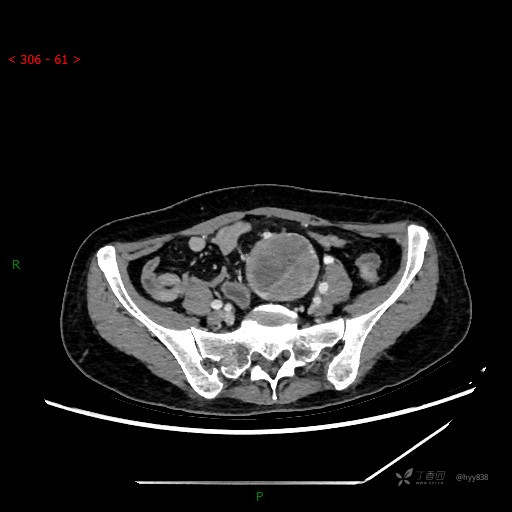

增强动脉期

静脉期